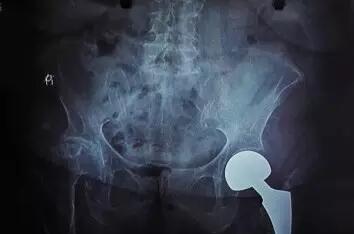

该患者,女性,86岁,干活时不慎摔倒,致左股骨粗隆间粉碎性骨折并股骨颈骨折来院。

骨伤科经内科、麻醉科会诊,围手术期管理,充分调整心肺功能,经过充分的术前准备,顺利完成了加长柄人工股骨头置换术。术后无各种并发症的发生,术后恢复良好,术后1周扶拐下地行走。